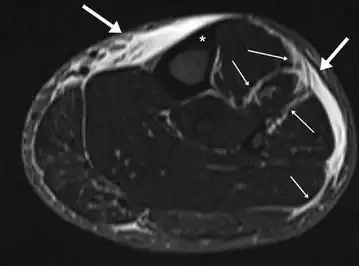

Other potential causes include stress fractures, compartment syndrome, nerve entrapment, and popliteal artery entrapment syndrome.[16] If the cause is unclear, medical imaging such as a bone scan or magnetic resonance imaging (MRI) may be performed.[3] Bone scans and MRI can differentiate between stress fractures and shin splints.[11]